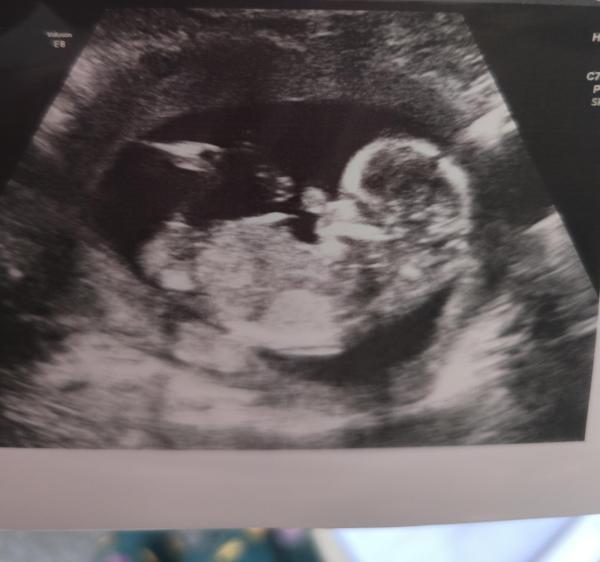

Schön das euer Termin so gut lief und das sind trotzdem schöne und deutliche Bilder.   Wir hatten diese Woche auch das ETS. Das lief zum GlĂŒck gut und die Blutwerte laut Nipt waren auch sehr gut. Die Herzklappe schließt noch nicht ganz, das ist ein Softmarker kann aber auch einfach Unreife und meine Ärztin sieht keinen Anlass fĂŒr eine weitere AbklĂ€rung, die Nackenfalte zb war 0,8. Ich bin gerade ganz aufgeregt, weil wir nĂ€chste Woche wegen des Geschlechts anrufen können. Da ich aber nicht weiß welchen ET sie angegeben haben (wurde korrigiert) kann Mittwoch oder Freitag heißen. Ich rufe am Donnerstag an, sind die Ergebnisse dann da freuen wir uns und ansonsten fahre ich Freitag vorbei, da ist es mir zu unsicher die telefonisch zu verpassen vor dem Wochenende.  Dann bin ich nĂ€chste Woche beim Betriebsarzt und es klĂ€rt sich ob ich ins BV gehe.    Liebe GrĂŒĂŸe

Bild zu